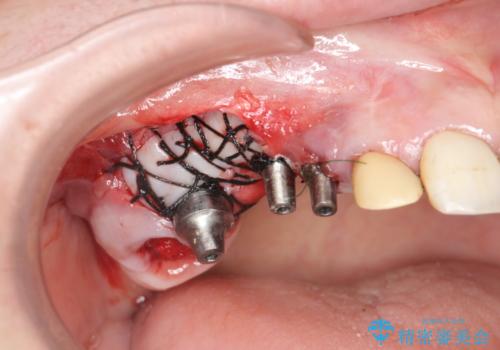

- 他院で1本インプラントを入れたまま治療に通うことができなくなり、途中からの治療を希望され来院されました。

既に埋入されているインプラントは位置が悪いのでそのまま骨内に留置することとし、新たに咬合機能を回復すべく3本のインプラントを埋入すると同時に吸収した骨幅を増やし、安定してインプラントで噛める環境整備を目指します。

- 120万円(インプラント×3 チタンカスタムアバットメント×3 メタルボンドクラウン×3 骨造成 歯肉移植)費用は治療当時の料金となります

インプラントが長持ちするために、インプラント周囲の十分な骨量・角化歯肉の存在・安定した咬合を一つづつ整備する治療を行いました。